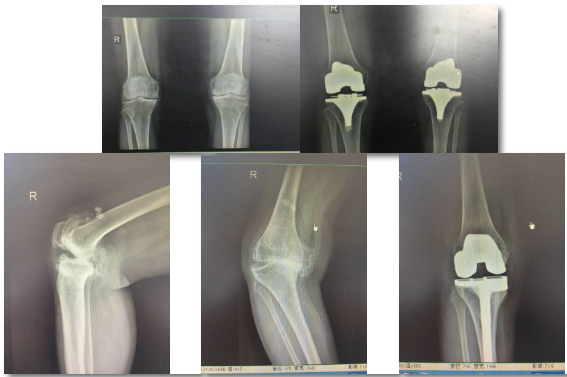

膝關(guān)節(jié)置換

嚴(yán)重膝關(guān)節(jié)疾病導(dǎo)致全膝破壞的終極治療是膝關(guān)節(jié)置換,骨二科采用內(nèi)軸膝系統(tǒng),能更好的模擬膝關(guān)節(jié)的正?;顒?,完美恢復(fù)膝關(guān)節(jié)的功能,達(dá)到Forget knee的效果。